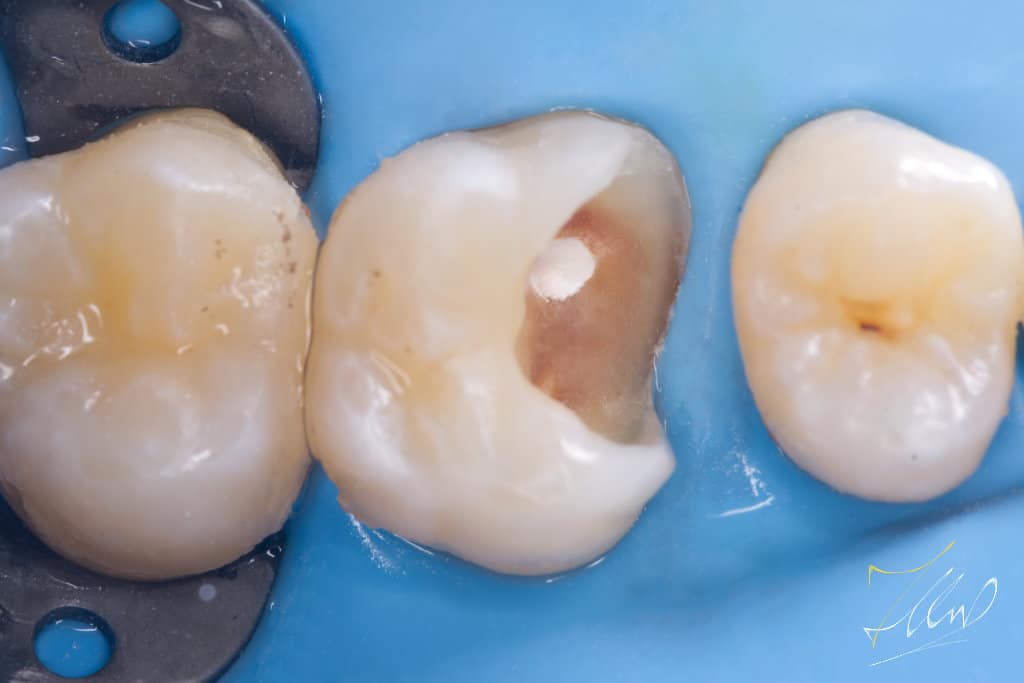

Upon initial examination, the patient reported experiencing temporary cold sensitivity and food stagnation in a specific area. The clinical diagnosis indicated that the tooth was vital, based on the Electric Pulp Test (EPT), the tooth is regarded vital, with initial response at level 36, followed by relief after 15 seconds.

When caries are removed and the pulp is exposed, it can weaken the enamel. In such cases, it is advisable to create a silicone index after covering the exposed pulp with mineral trioxide aggregate (MTA). This should be followed by a precise cavity design and the removal of unsupported buccal cusp .